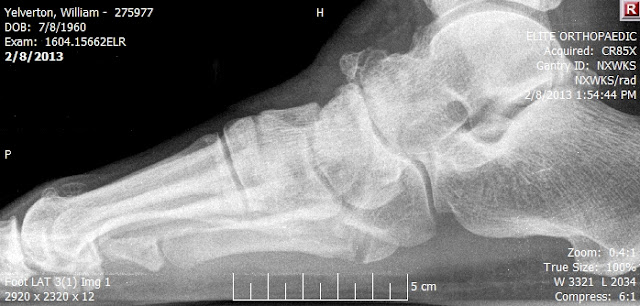

It is one of the most common foot injuries and can be caused by either a sudden injury or repeated stress over. The doctor can use a cast or other method to hold the injured foot in place while the fracture recovers. 5th metatarsal base fractures are common traumatic fractures among athletic populations that are notorious for nonunion due to tenuous blood supply. Fifth metatarsal fractures occur on an outer bone of the foot. Its name originates from its association with dancers who often sustain this injury when excessively twisting or rotating the. Anatomic and imaging evidence of a pathogenesis of avulsion of the plantar aponeurosis and the short peroneal. 5th metatarsal fractures have been quite common among elite soccer players in the english premier league over the past five years. If the bones are very close together and you're young and healthy and you protect the fracture site with the boot or a cast you could heal quite rapidly. We must distinguish between the acute traumatic fracture (let us call this a jones type. The majority of the time, these 5th metatarsal fracture not healing? Thais is sometimes called a jones fracture . For the first two weeks following your surgery. It is one of the most common foot injuries and can be caused by either a sudden injury or repeated stress over. This takes approximately 6 weeks of total immobilisation but time varies depending on severity. A jones fracture is a fracture of the 5th metatarsal of the foot. A common type of break in the part of your 5th metatarsal bone closest to the ankle is called a jones fracture. Related online courses on physioplus.